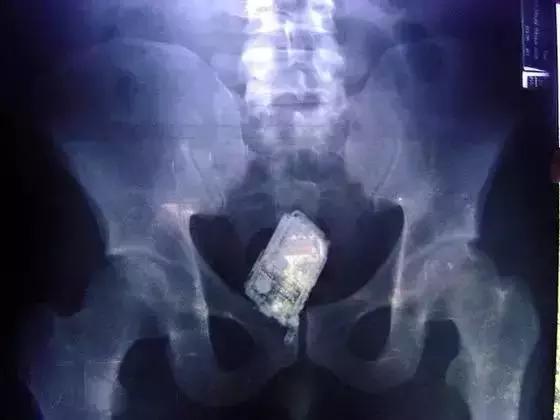

5、罪犯将*私走**的手机藏在体内